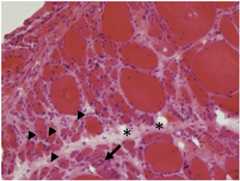

Histological findings of dermatomyositis:

Perifascicular atrophy (arrowheads) and inflammatory infiltrates (arrows) are characteristics of dermatomyositis.